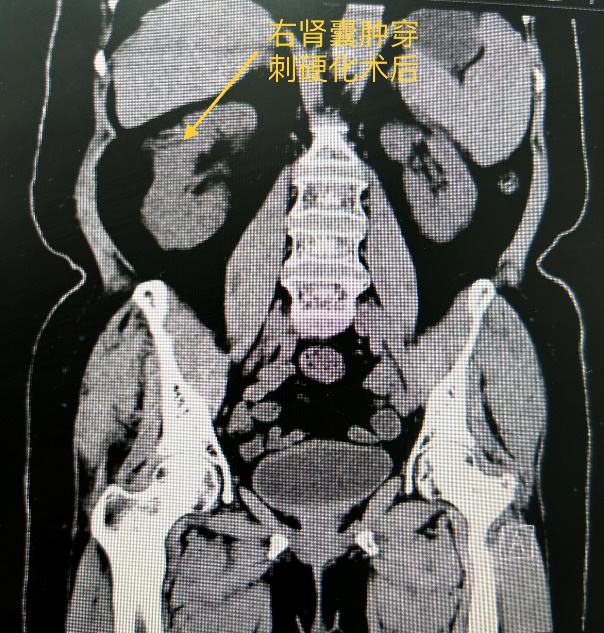

72岁的敏阿姨被腰痛症状困扰了5年,近日就诊于成人导航 肾病内科门诊,彩超提示“双肾囊性占位性病变,多考虑囊肿(右肾中极较大的54mm*45mm)”,泌尿系CT提示“双肾多发低密度病灶,考虑囊肿(右肾较大者48mm*36mm*46mm)”。经与患方沟通病情,决定行超声引导下肾囊肿穿刺硬化治疗术。

敏阿姨有高血压、糖尿病等多个慢性基础疾病,经完成充分的术前准备后,在超声科邢瑞林副主任超声引导下,由肾病内科陶小红副主任医师成功为敏阿姨实施肾囊肿穿刺硬化治疗术,术中抽出50ml囊内液体,并注入聚桂醇硬化剂,手术全程约半小时。手术后,敏阿姨觉得困扰她5年多的腰痛症状明显缓解,对治疗效果非常满意,术后次日出院回家。

疗效如何判定:随访复查超声时发现囊肿消失或直径小于1 cm为治愈;囊肿直径缩小 50%以上为有效;囊肿直径无变化或缩小不足1/4为无效。